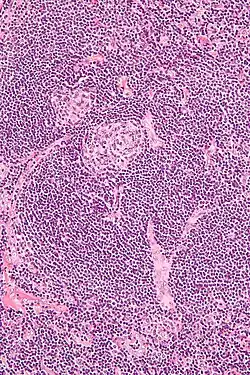

| Micrograph of lymph node biopsy demonstrating hyaline vascular features consistent with Castleman disease | |

The microscopic appearance (histology) of biopsied tissue from an enlarged lymph node must demonstrate a constellation of features consistent with Castleman disease. There are three patterns of characteristic histologic features associated with iMCD:[5]

- Hypervascular - regressed germinal centers, follicular dendritic cell prominence, hypervascularity in interfollicular regions, and prominent mantle zones with an “onion-skin” appearance.

- Plasmacytic – increased number of follicles with large hyperplastic germinal centers and sheet-like plasmacytosis (increased number of plasma cells).

- Mixed – features of both hypervascular and plasmacytic.

iMCD most commonly demonstrates plasmacytic features; however, hypervascular features or a mixture of both hypervascular and plasmacytic features may also be seen in iMCD lymph nodes. The clinical utility of subtyping iMCD by histologic features is uncertain, as histologic subtypes do not consistently predict disease severity or treatment response.